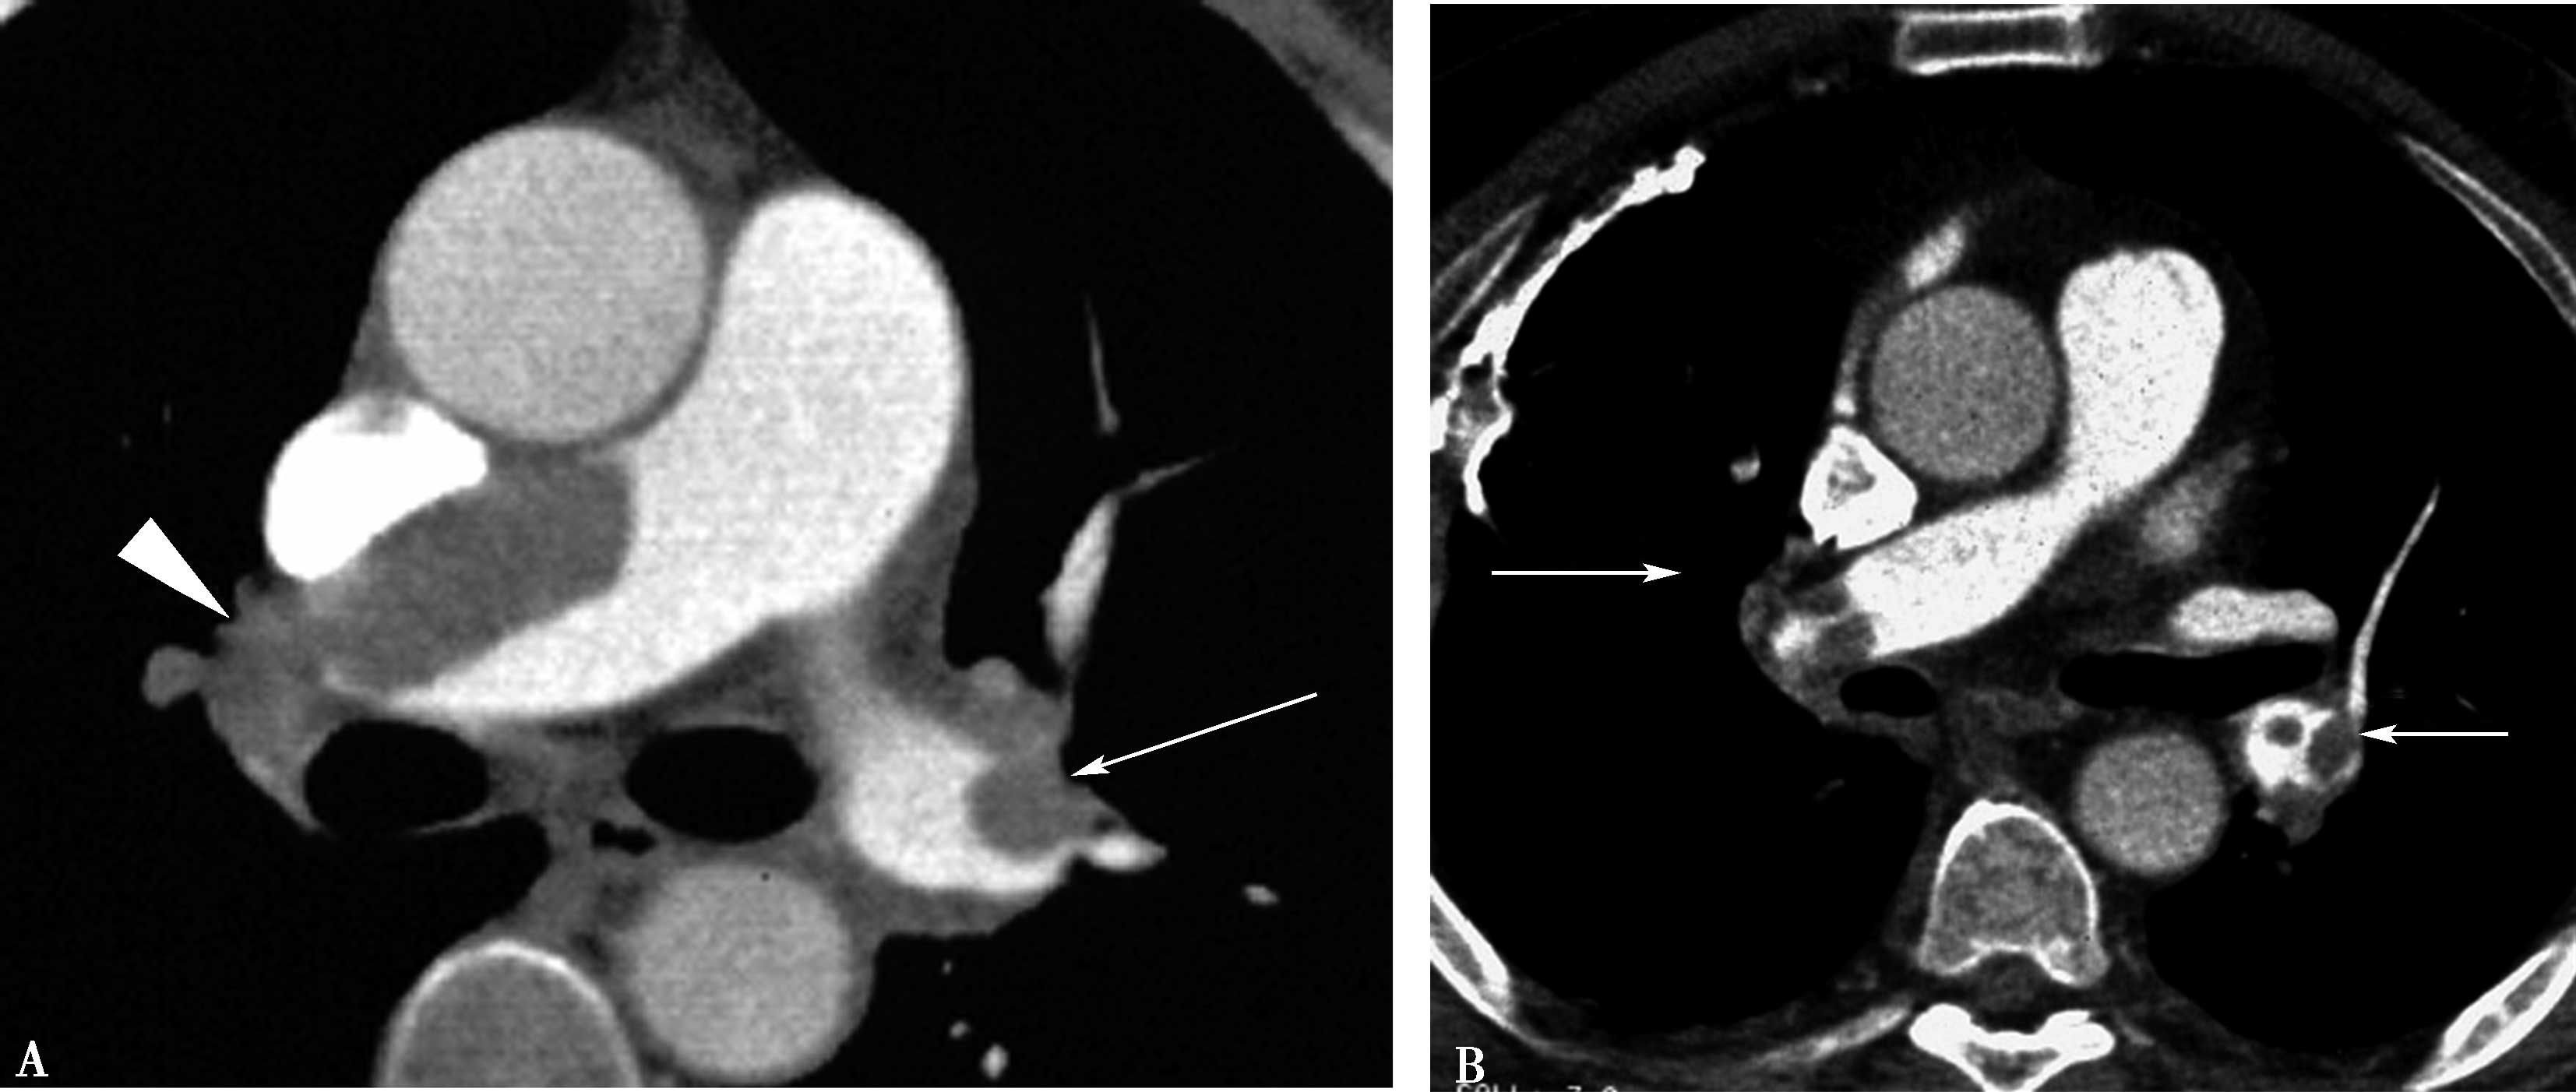

5.扫描采用对比剂智能自动跟踪触发技术,监测层面设定在气管分叉平面,ROI定位于肺动脉干,触发阈值定义为100Hu(图8-1-3,图8-1-4)。

图8-1-3 对比剂智能自动跟踪触发技术

造影剂智能自动跟踪触发技术能够准确获得扫描启动时间点并及时启动扫描

图8-1-4 常规肺动脉CT造影横断图及重建图像